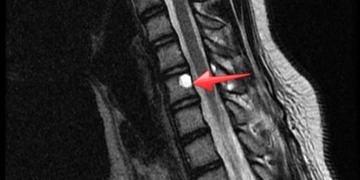

DevamıKemikler, kanserler arasında 3. sırada sıklıkla metastazın olduğu dokulardır. Omurga ise en sık kemik metastazı olan bölgedir. Akciğer, prostat, meme, böbrek, tiroid ve gastrointestinal sistemin primer kanserlerine...